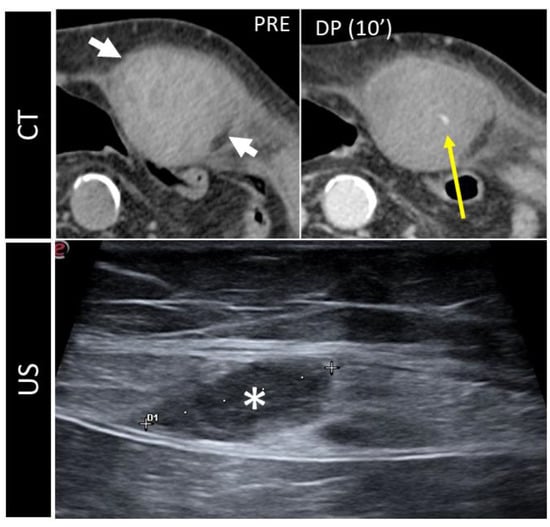

Figure 10. CT and US post-traumatic rectus sheath hematoma above the arcuate line. CT scan shows a well-defined mass, hyperintense on basal scan, in the context of the left rectus sheath (short white arrows). In the second picture, the delayed phase acquired 10 min after the injection of intravenous contrast demonstrates active bleeding (yellow arrow). The third picture shows the same lesion (*), studied some days later on US.